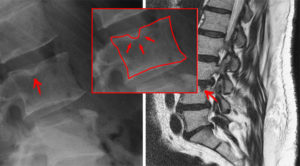

Грыжа Шморля: лечение, симптомы, чем опасна

Узелки Шморля (также известные как «Мелкие грыжи Шморля») – явление нередкое. Хотим предварительно уточнить, собственно, что означает термин «Дисковая Грыжа». Говоря о таком явлении как грыжа Шморля, что это такое и как лечить ее, то врачи отмечают, что это выпуклость хрящевой ткани между позвонками с дальнейшим ущемлением и воспалением корешков спинномозговых нервных окончаний.

Формирование начинается, когда хрящевая ткань замыкательных пластинок проваливается в тела позвонков деформирую губчатую кость. Иными словами, происходит вдавливание диска в тела верхнего, нижнего позвонка.

Так именно эти пустоты и провоцируют в будущем саму суть проблемы – постепенно в них проваливаются замыкательные пластины позвонков. Чаще всего такая патология как узелковое новообразование Шморля локализовано в грудном или поясничном отделе позвоночника (в средней или нижней части спины).

Такие негативные и предрасполагающие факторы чаще всего диагностируются врачами в период активного роста ребенка, либо же при интенсивных физических или же эмоциональных нагрузках на организм, что характерно для спортсменов. Как следствие стечения негативных факторов – плотный узел хрящевой ткани будет изнутри давить на само тело позвоночного столба и провоцировать его деформирование. Это все достаточно четко видно на рентгеновских снимках.

Рентгеновский снимок межпозвоночной грыжы шморля Рентгеновский снимок межпозвоночной грыжы шморля1